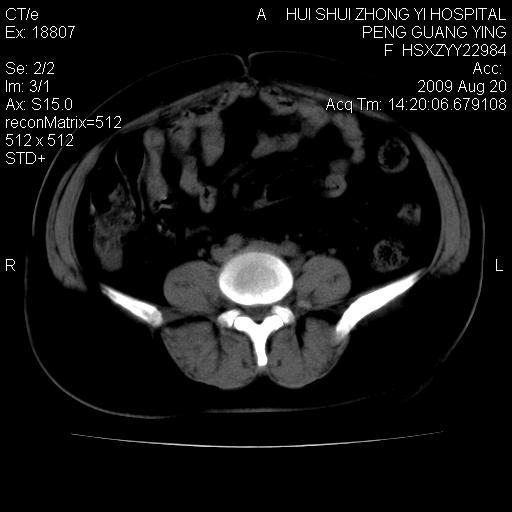

标题: CT21707:女,42岁,因发现下腹部包块2月。 [打印本页]

标题: CT21707:女,42岁,因发现下腹部包块2月。

病灶来源——子宫?附件?

从平扫角度看本人还是倾向于子宫肌瘤诊断,宫腔少量积液。

目前的影像表现显示肿块位于腹腔及盆腔,但具体定位,分清来源较困难,是否来源于卵巢、子宫无法定论,子宫直肠及子宫膀胱周围脂肪间隙尚较清晰,如果患者有过腹腔好或者盆腔手术史,也可以形成不典型的血中,最好手术后定为定性,我期待结果。

软组织密度,与子宫一致。双侧卵巢形态、密度好,不支持来源于卵巢。

病史不全面,病灶来源可能是子宫或卵巢,若临床有剖腹产、痛经史,则更支持前者,亦更支持子宫腺肌症